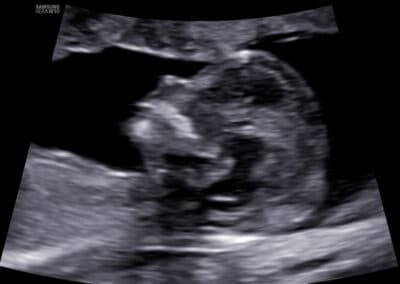

Protokol pro správné vyšetření nosní kůstky:

CRL 45-84 mm (11-13+6 týden) Přesná mid-sagitální rovina (echogenní špička nosu a patro vpředu, diencefalon v centru mozku a nuchální translucence vzadu, nesmí být vidět processus frontalis maxillae) Zvětšení (hlava a hrudník plodu vyplňují většinu obrazovky) Paralelní průběh povrchu sondy s povrchem nosu Separace nosní kůstky od kůže (dvě echogenní linky) Echogenita nosní kůstky musí být při její přítomnosti vyšší než je echogenita kůže na povrchu nosu Pokud je linka nosní kůstky tenčí a méně echogenní než je linka povrchu kůže nosu, jedná se abnormální nález- nosní kůstka chybí